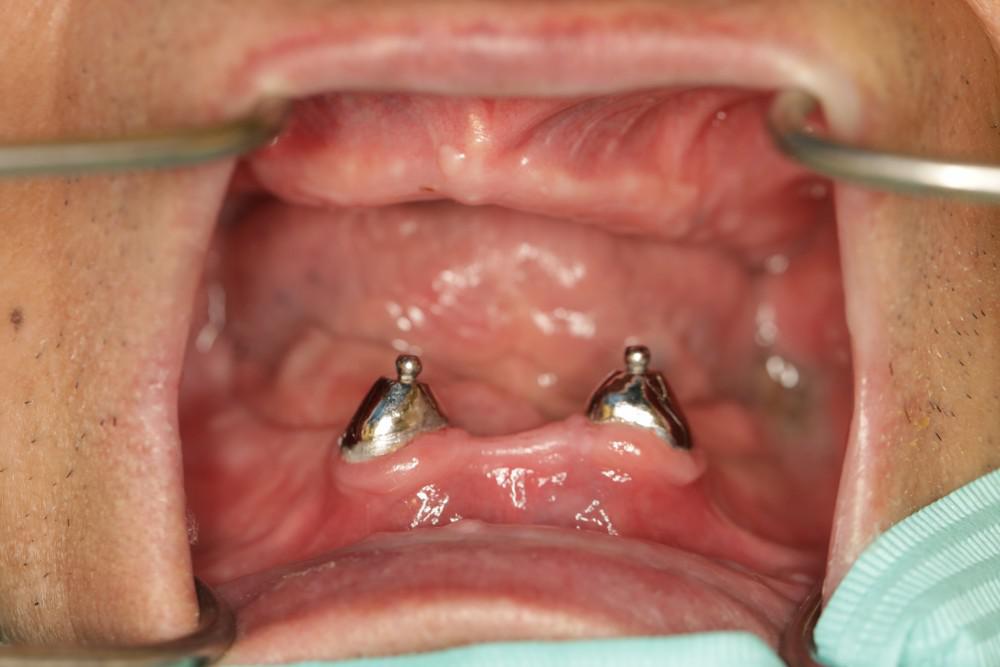

Prosthodontist Qing used accurate impression, functional molding, and neutral zone technique to fabricate high-quality regular dentures.

Though without implants the denture can stay tight enough to serve the patient's daily oral function.